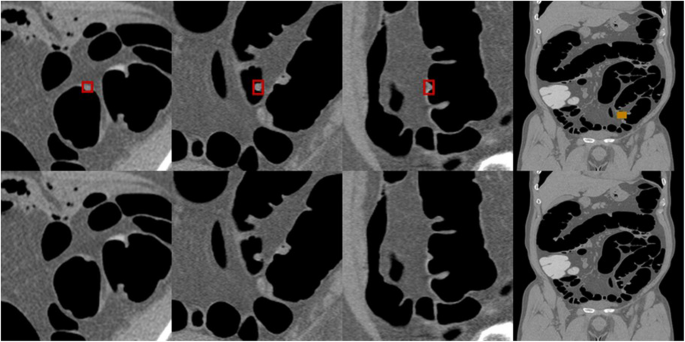

Fig. 2 shows an example of annotation indicating the extent of a colorectal tumor and its coordinates in a CT image used for the development of an AI algorithm. Data regarding the lesion location and size (i.e., circumscribed rectangle) were specified based on the colonoscopy findings and the correct number of lesions included in the CT colonography images used for training and validation. The annotation process and training were carried out by radiologists with experience in reading CT colonography; however no strict rules were imposed. The training and internal validation set were completely randomized during division. Lesions smaller than 6 mm were not assessed in this study.

Annotations for colorectal lesions. Annotation of the bounding rectangle surrounding the colorectal lesions known a priori to be correct on the CT image. CT: computed tomography.

An example of a case in which a lesion within the residue could be detected with low-dose pretreatment and poor tagging is shown in Fig. 5. This lesion was thought to be difficult to detect using CAD that was designed with conventional lesion morphologies that should be detected by a human. The AI algorithm used during this study was able to correctly detect lesions buried in such residue in some cases.

Example case of detecting a lesion embedded in tagging residue. Arrow indicates the lesion of interest.